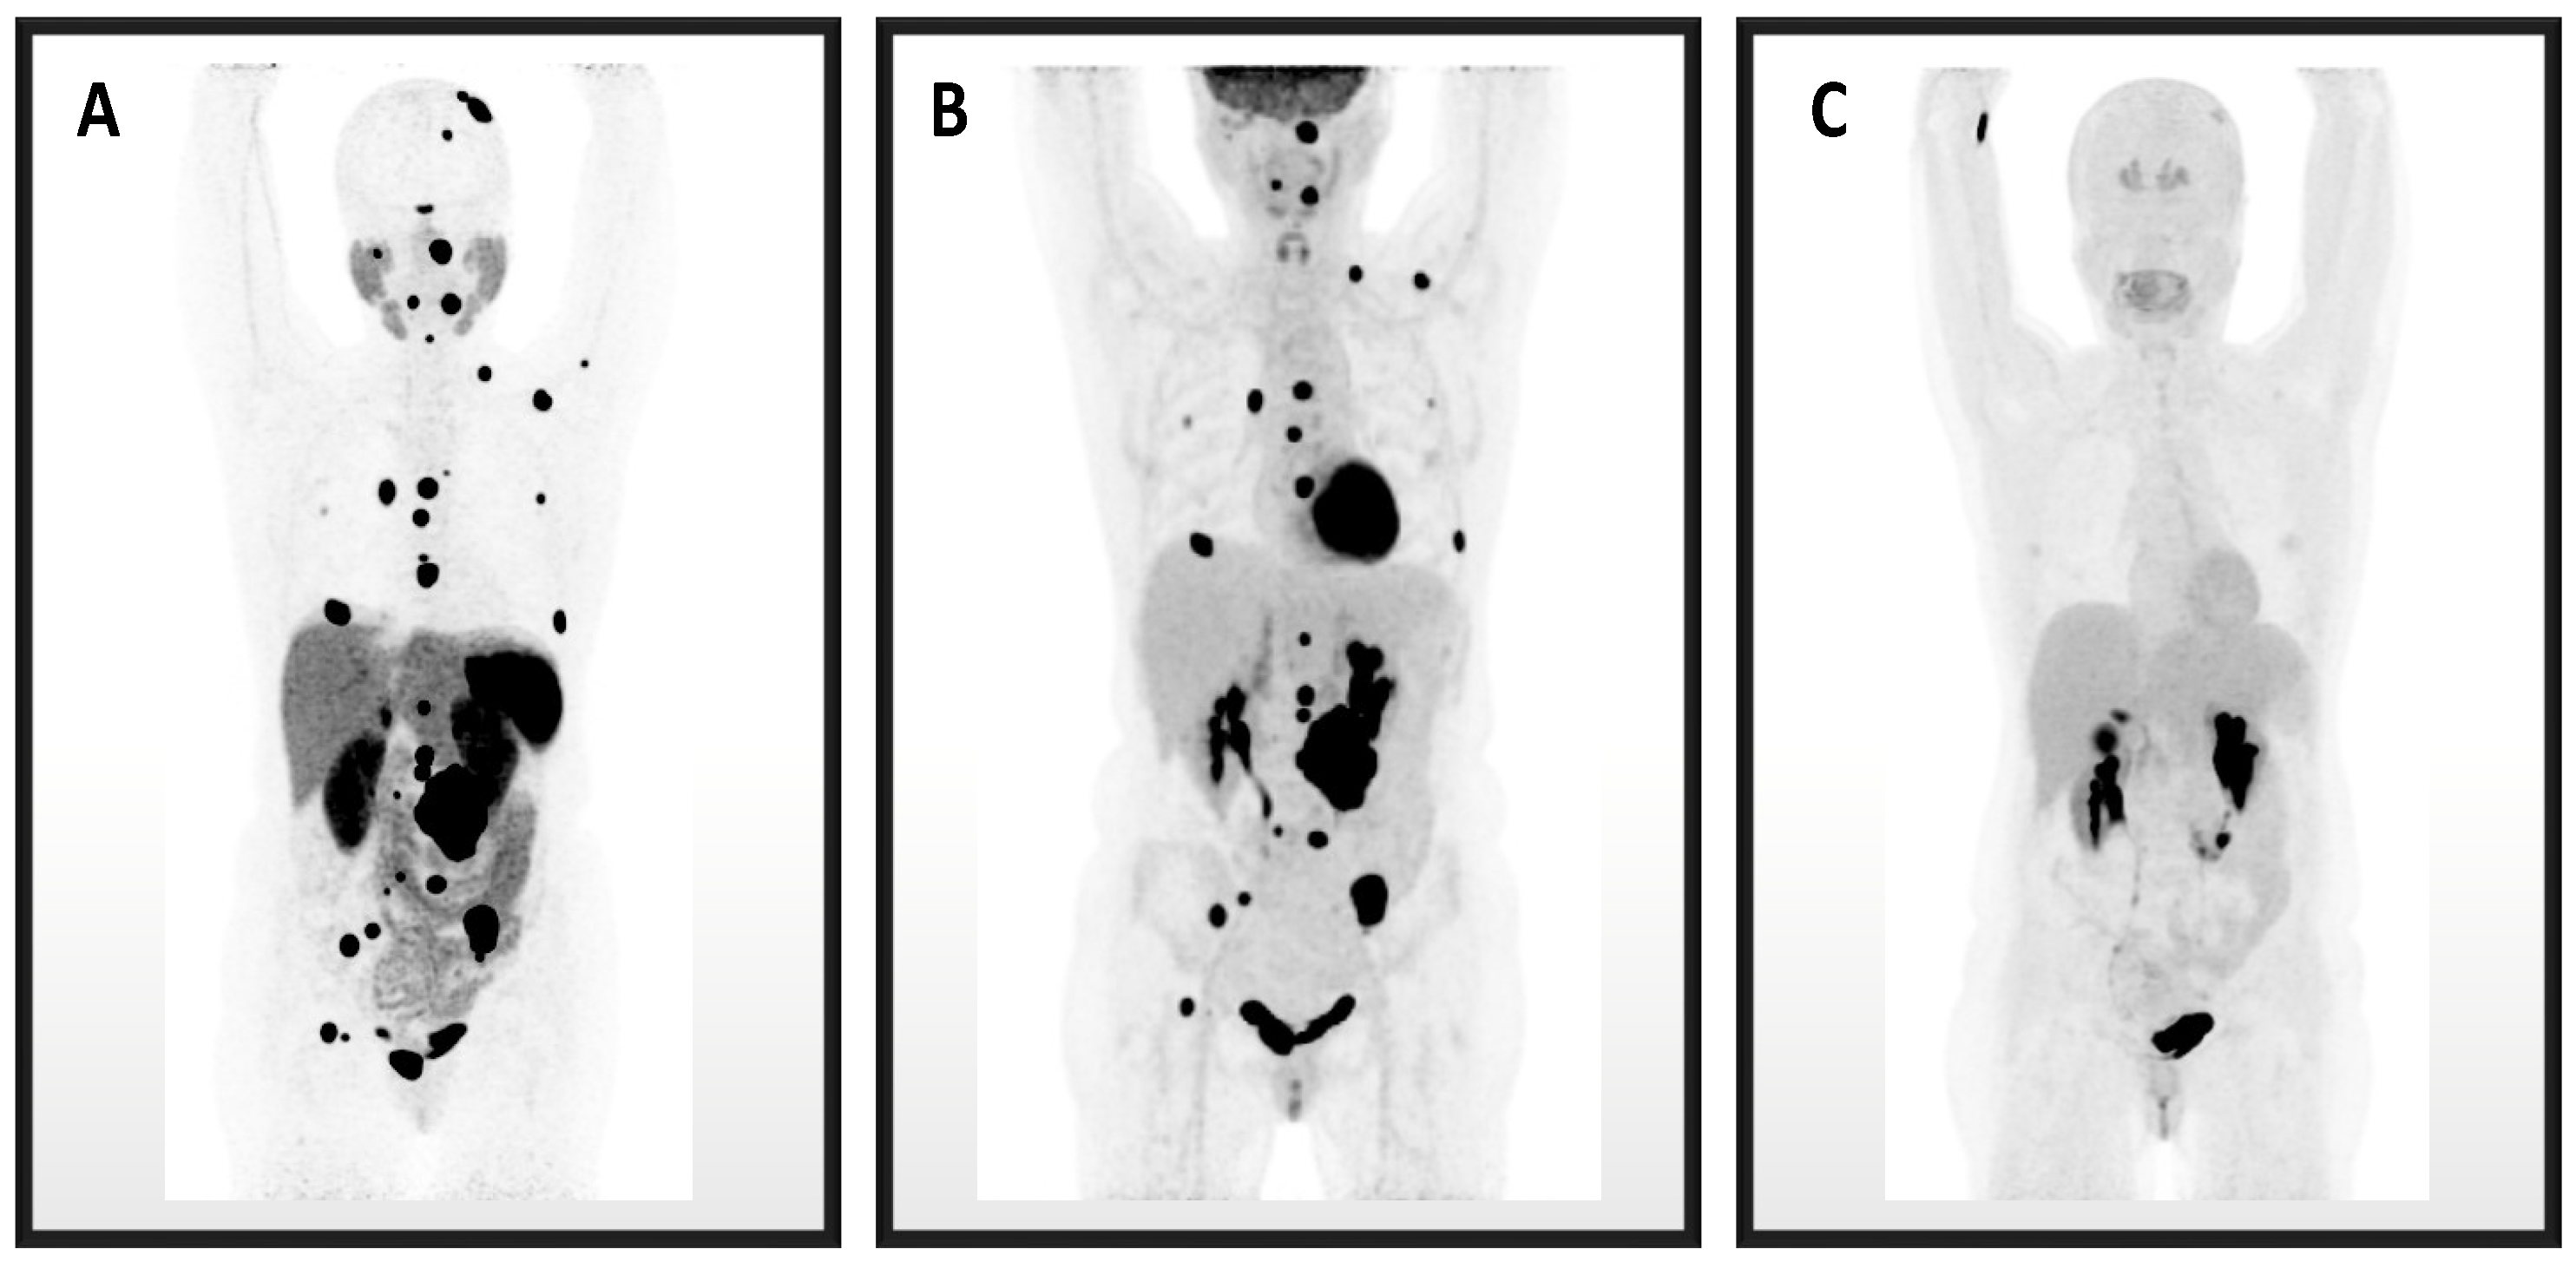

3.6. Patients with Four Imaging Modalities